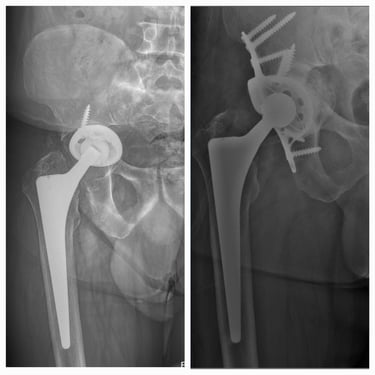

Artroplastia de cadera (prótesis total/parcial).

Cirugía de revisión de cadera y rodilla.

Casos complejos y manejo de complicaciones de cadera y rodilla

Manejo de secuelas y complicaciones de prótesis de cadera y rodilla.